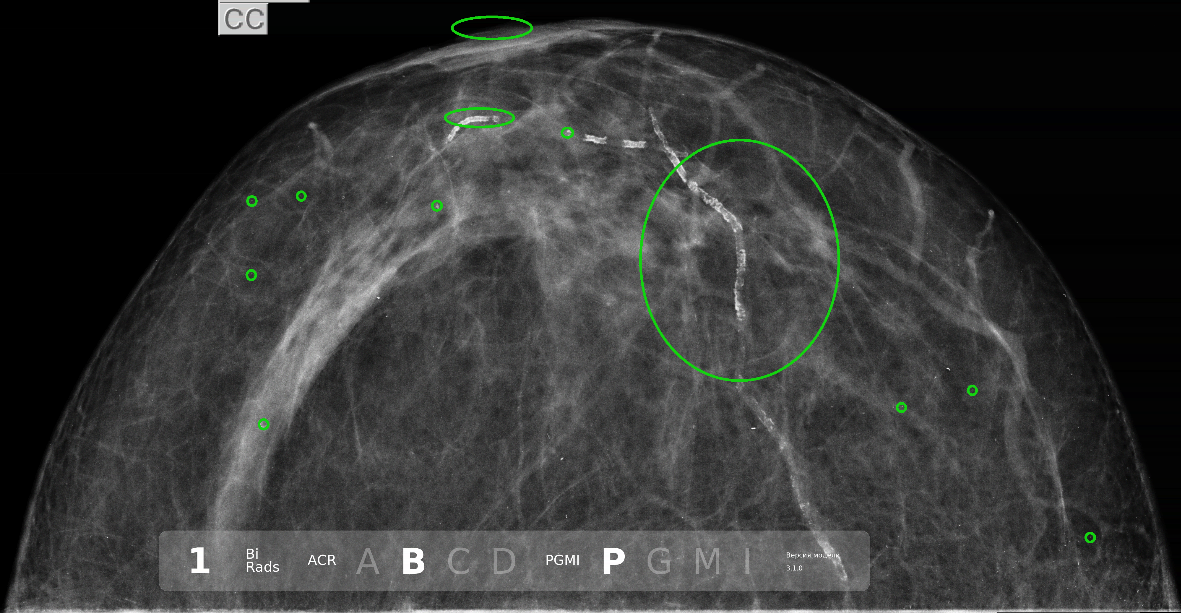

Результаты были довольно дикие - на исследовании предсказались только доброкачественные кальцинаты, причём явно не того размера и не в тех местах, где нужно.